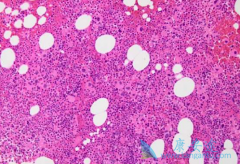

不同的给药途径会影响药物在体内的有效浓度,与疗效关系密切,用药合理与否,关系到治疗的成败。 来那度胺 (Revlimid)作为靶向药,一半是持续使用,直至肿瘤进展或患者不耐受。那来那度胺的吃法与治疗效果有关系吗?来那度胺在治疗多发性骨髓瘤与套细胞 ...

来那度胺 (瑞复美)作为沙利度胺的类似物,为了防止来那度胺可能会导致胎儿出现缺陷或死亡。所以,育龄中的女性在使用来那度胺前都必须进行以下事项:妊娠检测根据当地医疗实际,必须在医生监督下对有可能怀孕的女性进行妊娠检测,要求检测的灵敏度至 ...

来那度胺 (雷利米得)是一种免疫调节药物,该药物具备多种作用机制,在分子水平上,来那度胺已被证明与泛素E3连接酶相互作用并靶向该酶降解Ikaros转录因子IKZF1和IKZF3。也就是说来那度胺的致畸和抗肿瘤性质是可以被分离。因此后期来那度胺逐渐从血液 ...

说到 来那度胺 (lenalidomide),为人熟知的就是在治疗多发性骨髓瘤和骨髓异常综合征的疗效显著;最新的一项研究表明,在治疗肝癌的过程中,来那度胺也发挥重要作用。一项研究中将40例多吉美治疗失败的晚期肝癌患者作为研究对象,观察来那度胺25mg,一天一 ...

雷利度胺 (来那度胺)是一种作用机制比较复杂的药物,其作用包括抑制肿瘤坏死因子а、白介素-6和IL-12,诱导Caspase-8介导的凋亡、抑制细胞黏附和血管生成,通过诱导白介素-2和干扰素г刺激T和NK细胞增殖,抑制Akt磷酸化等。很多患有骨髓增生异常综合 ...